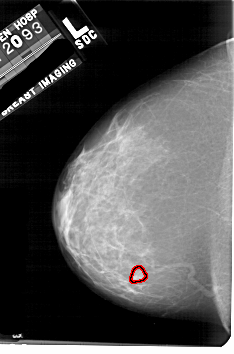

A_1758_1.RIGHT_MLO

RIGHT_MLO LINES 5206 PIXELS_PER_LINE 3376 BITS_PER_PIXEL 12 RESOLUTION 43.5 NON_OVERLAY

FILE: A_1758_1.LEFT_CC.OVERLAY

TOTAL_ABNORMALITIES 1

ABNORMALITY 1

LESION_TYPE MASS SHAPE LOBULATED MARGINS OBSCURED

ASSESSMENT 3

SUBTLETY 4

PATHOLOGY BENIGN

TOTAL_OUTLINES 1

BOUNDARY